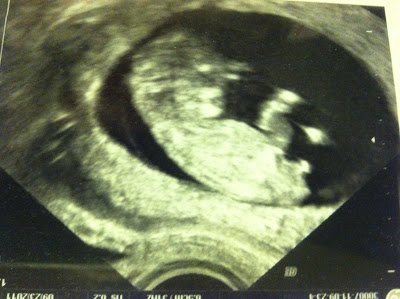

We had our 20 week ultrasound yesterday. I would have been way more excited if we were finding out the gender, but we found out very early that it was a boy! It's very unusual to find out the gender at a 12 week sonogram, but there was absolutely no way to deny that this is a little boy.

That's him at 12 weeks. You can even see his pee pee....dooter....package? from the side. Definitely a boy :) Our ultrasound yesterday confirmed it.

What a creepy face, right?